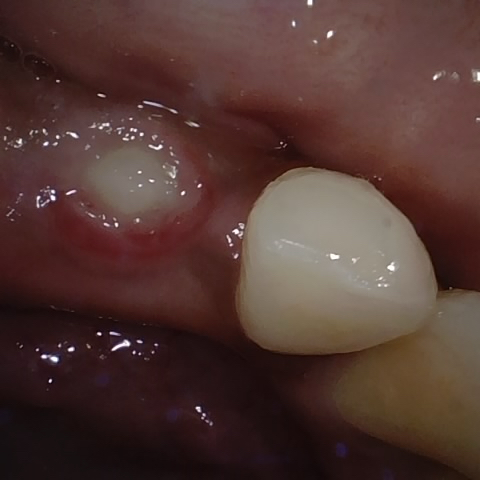

Annotated as "Good"